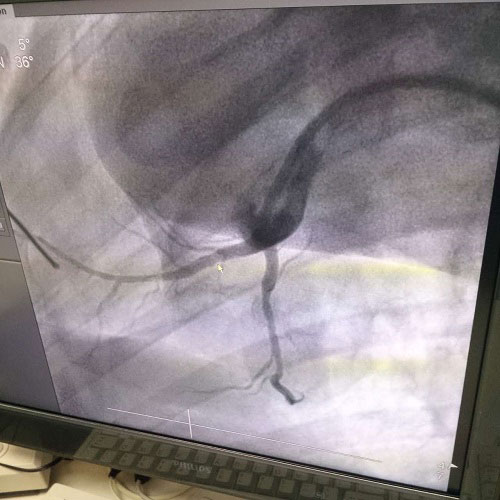

生物全降解鎂合金藥物洗脫支架是我由公司自主立項研發(fā)、主要工藝技術(shù)完全自主,具有完全自主知識產(chǎn)權(quán)。并且可行性強,前期研發(fā)基礎(chǔ)扎實,市場需求迫切,實施風(fēng)險可控,屬全球同行業(yè)領(lǐng)先技術(shù),填補國內(nèi)技術(shù)發(fā)展空白,符合國家產(chǎn)業(yè)發(fā)展政策,社會、經(jīng)濟效益巨大。目前鎂合金藥物支架已進入動物實驗階段,植入動物體內(nèi)一個月之后效果良好。